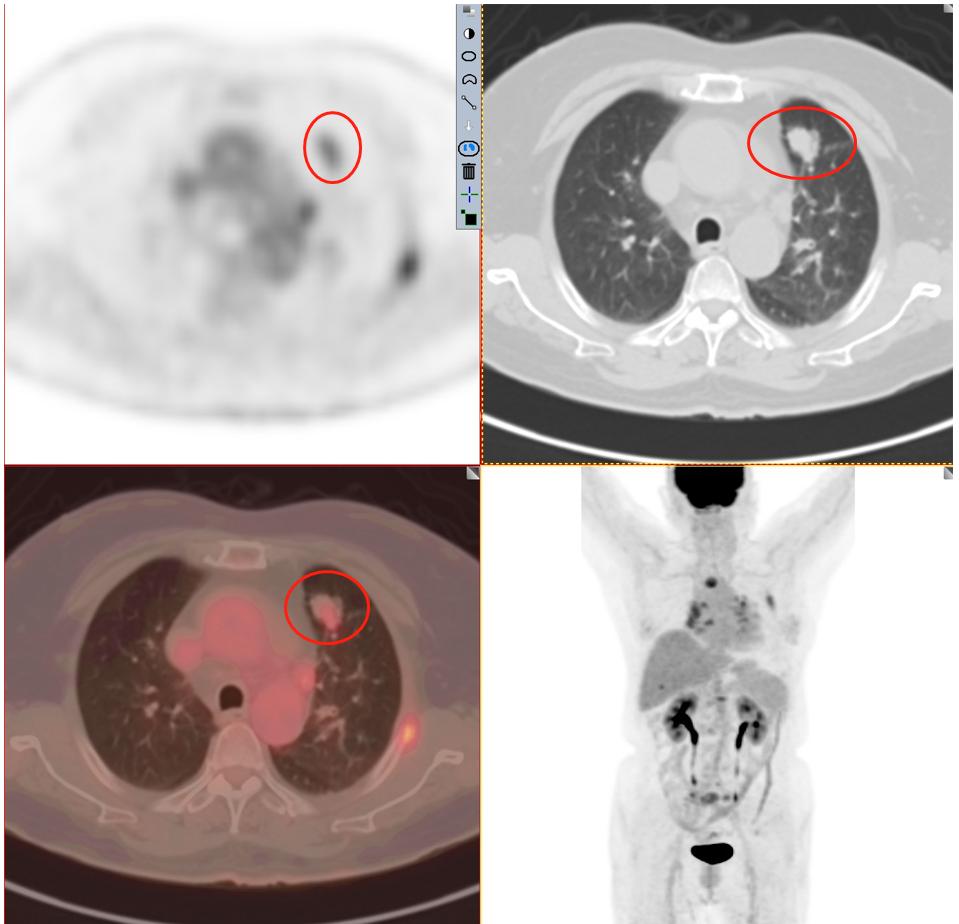

患者1:图3

毫无疑问PET/CT检查18-F-FDG葡萄糖代谢增高,再一次增强了肺癌的诊断信心,影像学可以肯定的诊断为周围型肺癌。其余所示结节未见FDG代谢增高,考虑为慢性炎性结节及钙化灶。

患者1:图4

全身PET/CT检查其他部位未见明显异常放射性浓聚灶,即全身其他部位未发现肿瘤性病变(未见明确转移)。不幸中的万幸,患者没有转移。通过检查可以进行一个肿瘤分期:T1cN0M0 属于ⅠA3期。这一类也算早期肺癌,术后治愈率不错。